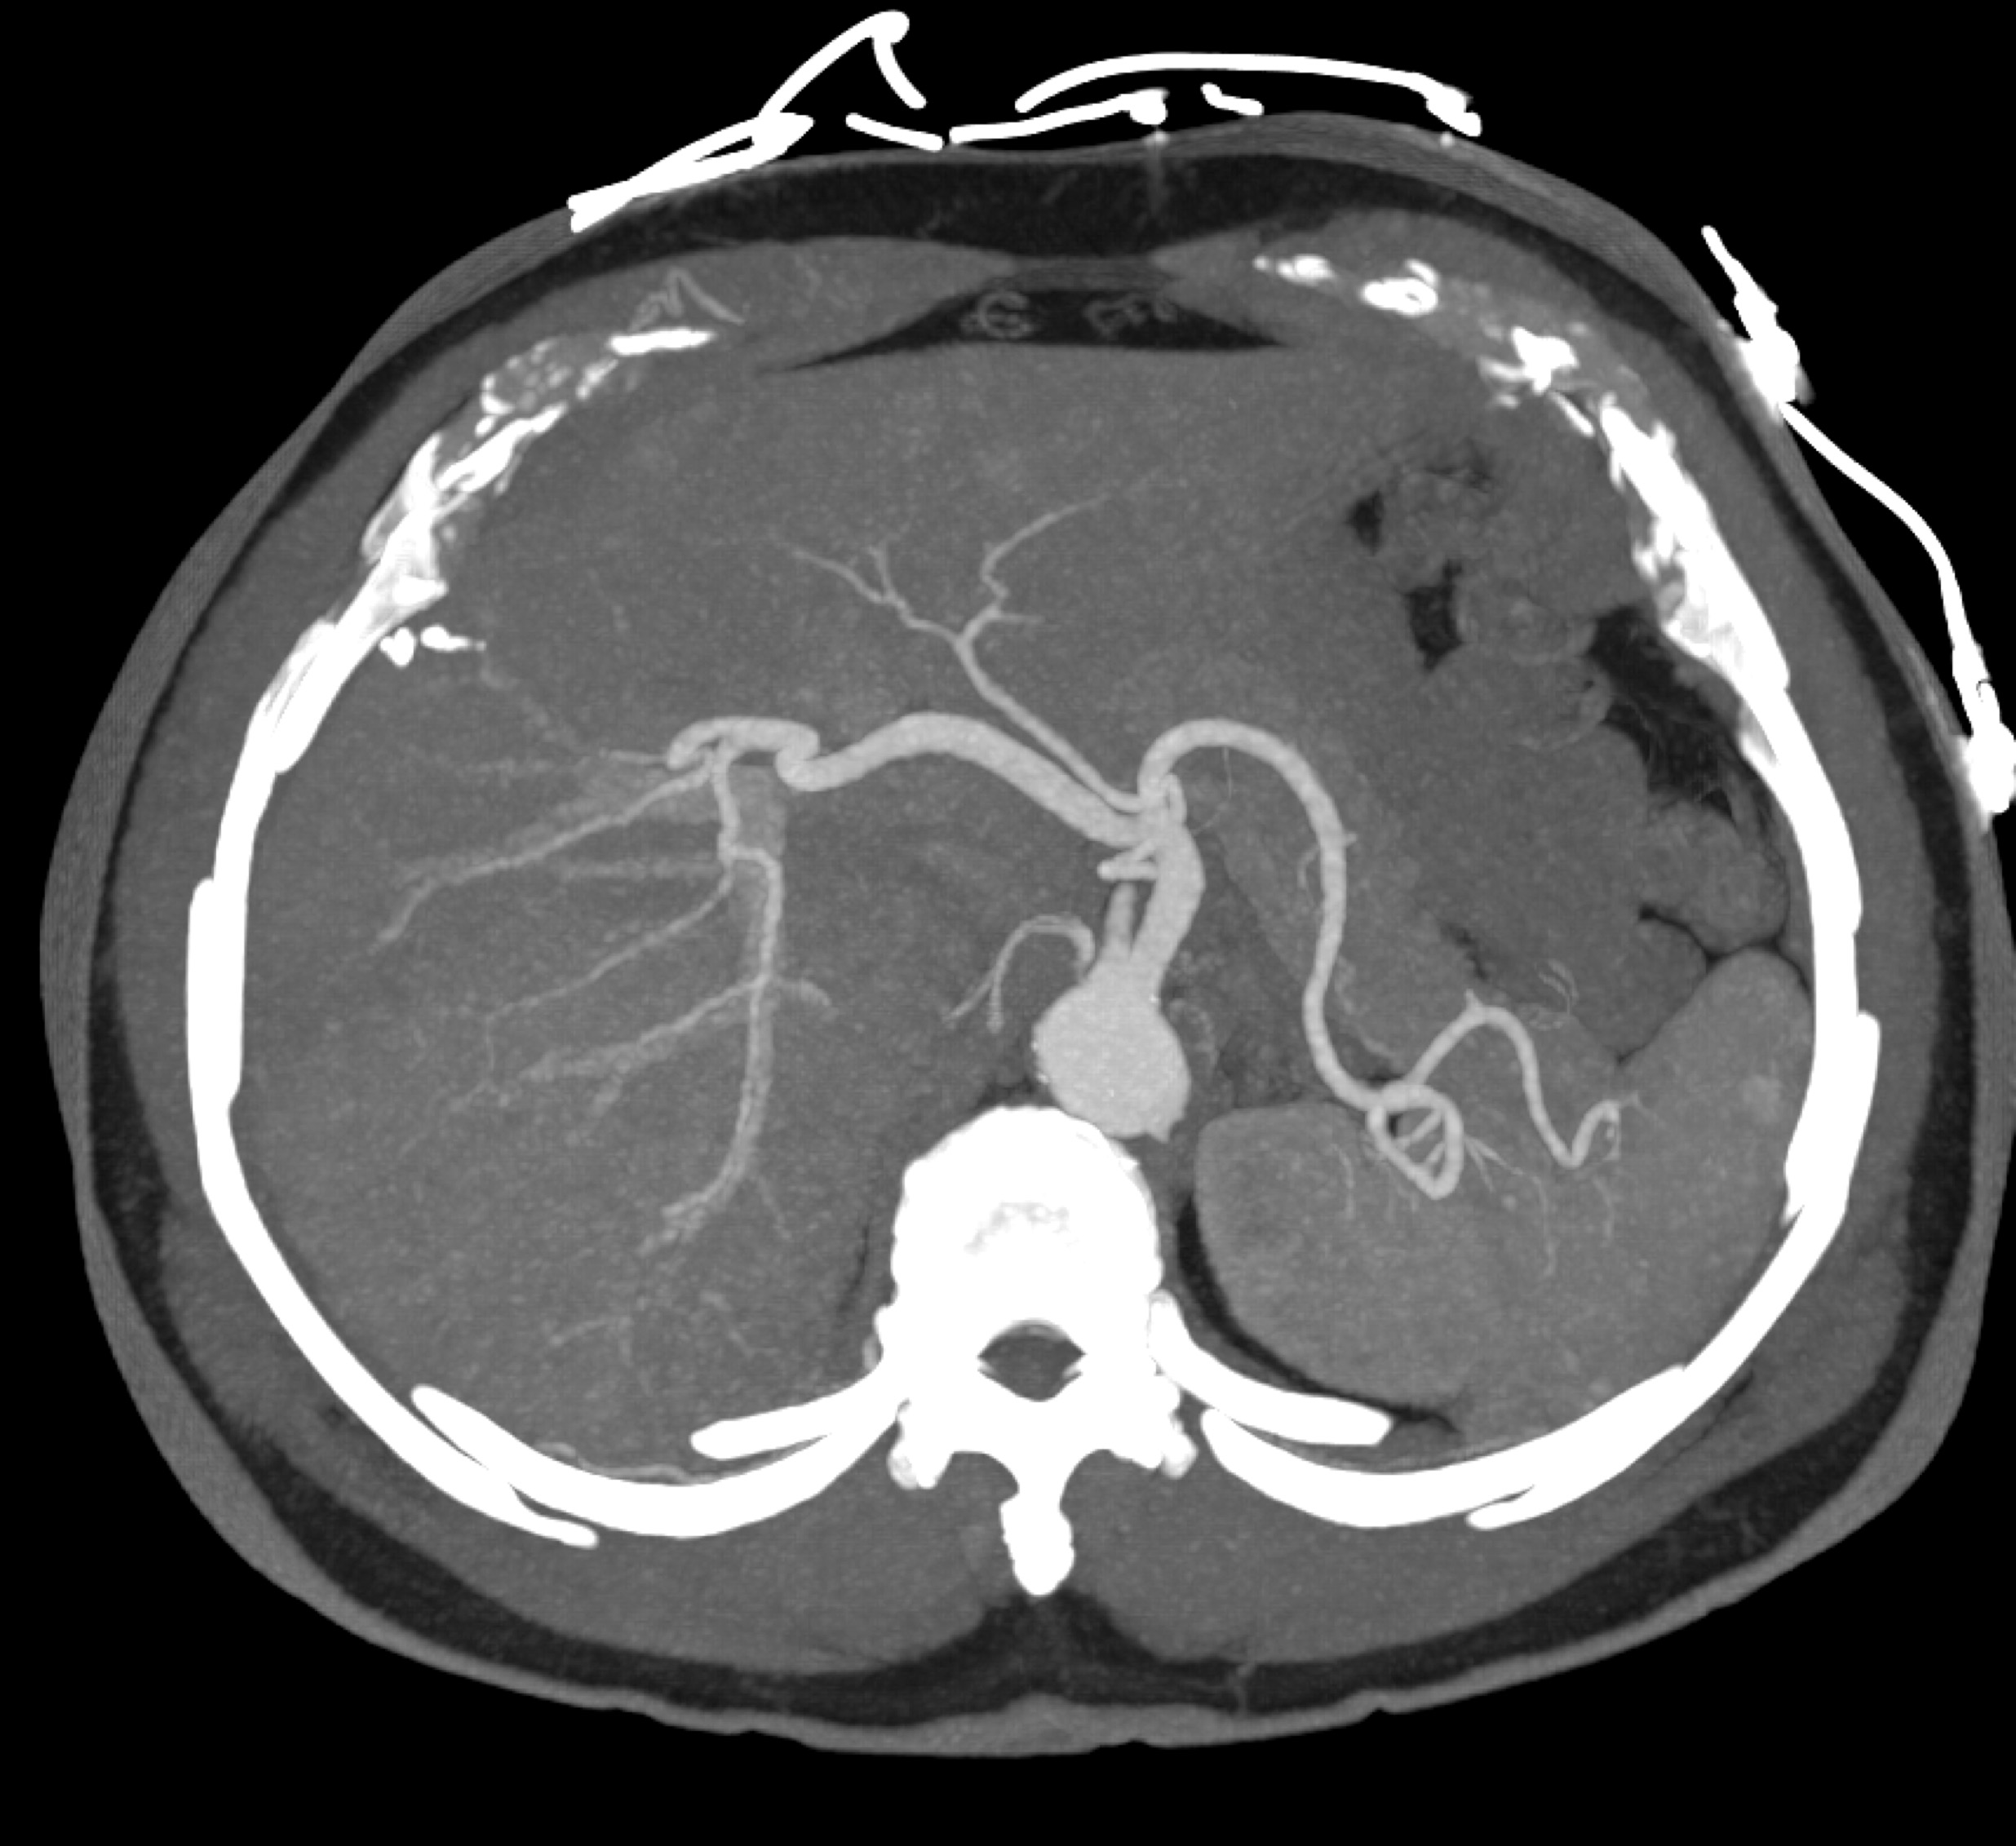

7) The most likely diagnosis in this case is ?

cholangiocarcinoma

metastatic colon cancer

metastatic neuroendocrine tumor

hepatoma